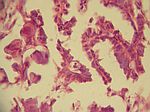

Psam. Ovarial-Ca (Netzmetastase), HE